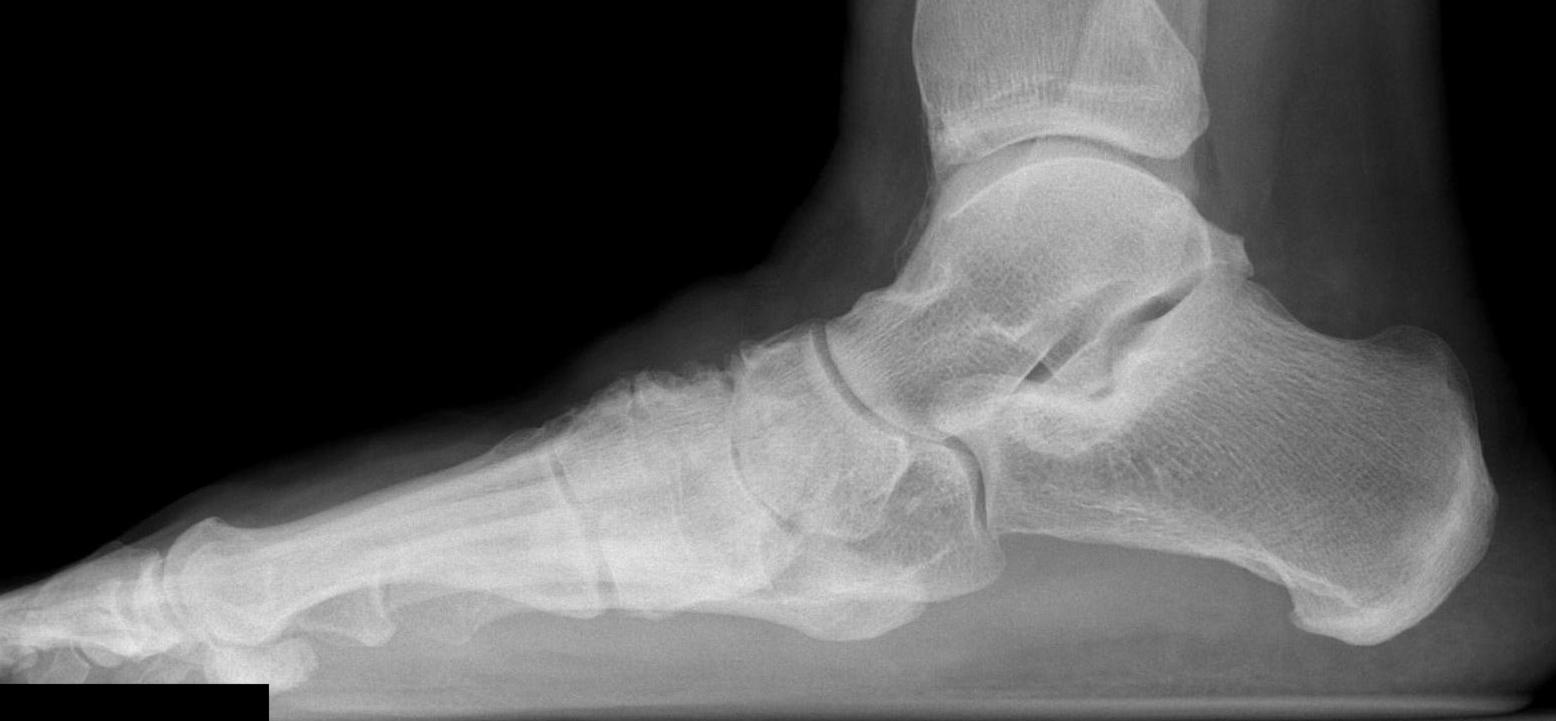

Planovalgus secondary to Charcot